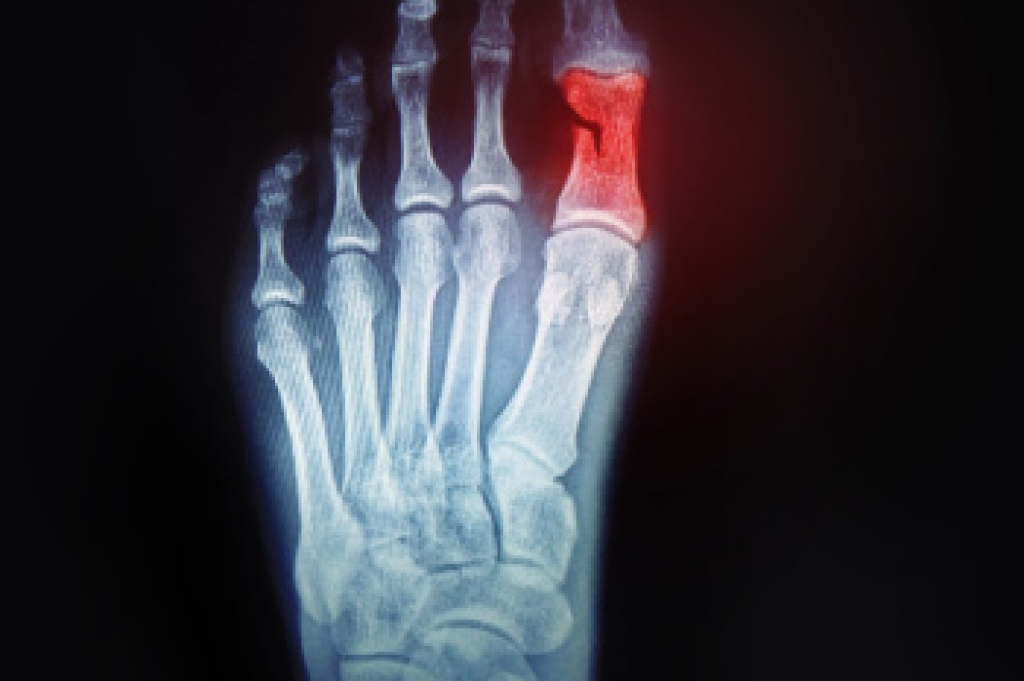

To figure out the cause of foot pain, podiatrists utilize several different methods. This can range from simple visual inspections and sensation tests to X-rays and MRI scans. Prior medical history, family medical history, and any recent physical traumatic events will all be taken into consideration for a proper diagnosis.

- Injury (from stress fractures, broken toe, foot, ankle, Achilles tendon ruptures, and sprains)